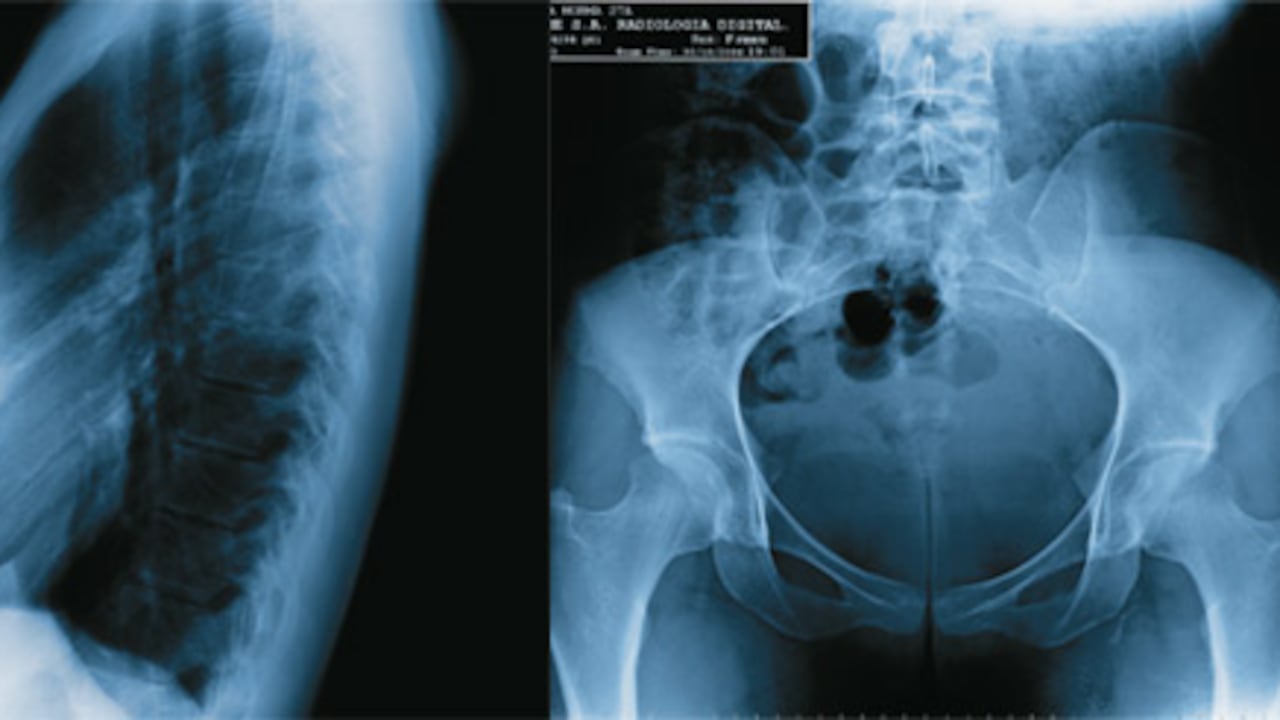

Tiene prótesis en los senos. Toda la zona cardiovascular tiene una adecuada posición. Mide 1,83 y su radiografía del tórax es normal. Los pulmones no muestran cuerpos extraños. Los tejidos blandos y toda la estructura ósea del tronco no muestra alteraciones. La radiografía de la pelvis tiene una estructura ósea adecuada y sana. Todas las relaciones articulares tienen características normales.